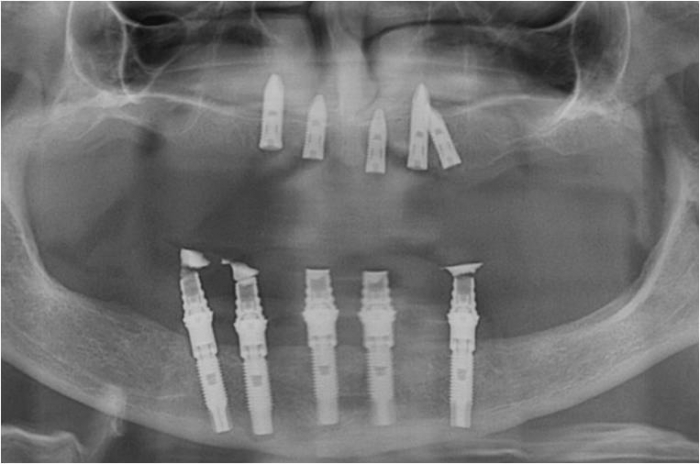

Raio X inicial

Rx após extração dos dentes e instalação de 05 implantes e prótese fixa imediata

Raio X dos implantes superiores